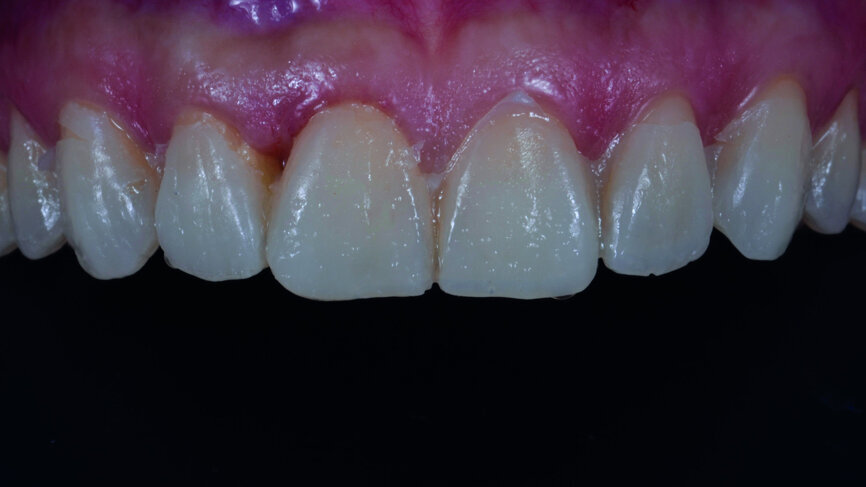

Fig. 7: Periodontal tissue of the anterior teeth six months after crown lengthening.

After six months of tissue stabilisation (Fig. 7), a mock-up was produced with Telio CS C&B (Ivoclar Vivadent) chairside (Figs. 8a & b), and tooth preparations with silicone guides were performed (Figs. 9a–c). Both conventional impressions with polyvinylsiloxane (Fig. 10) and digital impressions (TRIOS, 3Shape) were taken (Fig. 11).